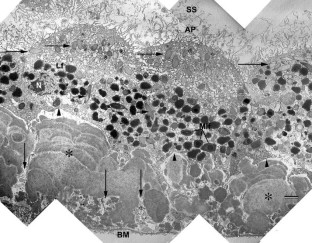

A 78-year-old woman with AFVD underwent MT with 360° retinotomy 3–4 months after loss of reading ability. Most of the vitelliform material was lost during surgery; the subfoveal tissue was excised, fixed in aldehydes, postfixed in reduced OsO4 and embedded in epoxy resin. Semithin sections were stained with toluidine blue for light microscopy (LM) and thin sections with uranyl acetate and lead citrate for transmission electron microscopy (TEM).

Postoperatively, the patient developed a retinal detachment complicated by proliferative vitreoretinopathy (PVR) requiring two additional vitreoretinal procedures before finally the silicone oil could be removed. Twenty-two months after MT the distance visual acuity was unchanged at 0.2; the near visual acuity had improved from less than 0.1 before MT to 0.4. The retina was completely attached. LM and TEM revealed serious alterations indicative of a breakdown of the outer layer of the retina.

Through the present single case it is not possible to determine whether MT could be a therapeutic approach in patients with AFVD. The most important cause for the limited postoperative visual improvement seems to be a primary injury of the foveal function due to the AFVD. This is supported by the extensive subfoveal degeneration and necrosis affecting not only the RPE cells but also their basement membrane and the interposed basal laminar deposits.